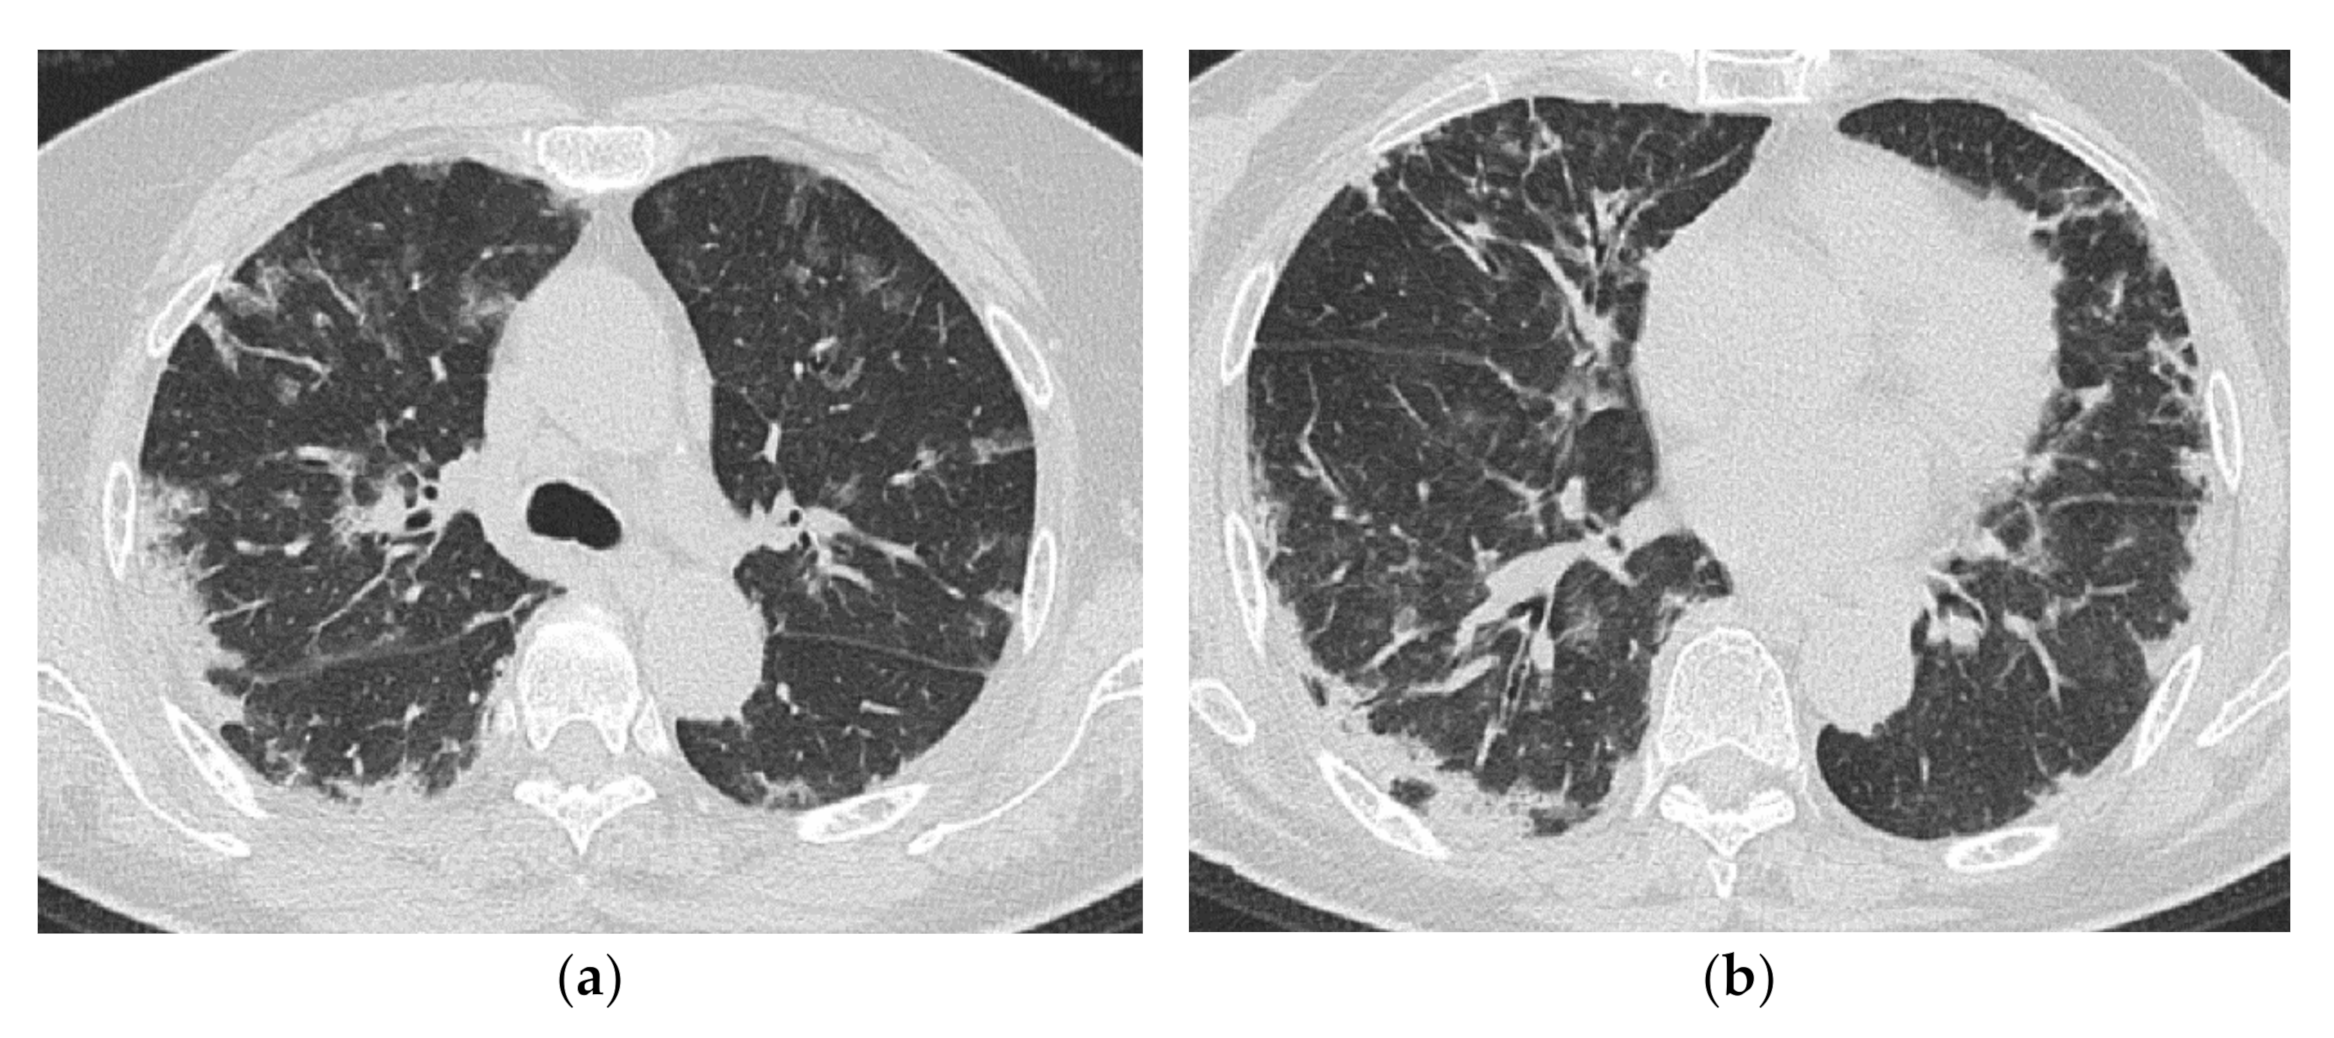

2.2. Acute Type

| Predominantly in the lower lobes of both lungs | Diffuse, or diffuse with a predominance of the lower lung zone |

| Peribronchovascular bundle distribution | Peribronchovascular distribution in the lower lobes, with parallel extension to the pleura |

| Reticular shadows and consolidation are common | GGO and consolidation |

| Reduced volume of the lower lobes | Basal volume loss |

4. HRCT Findings in Relation to the Poorer Prognosis